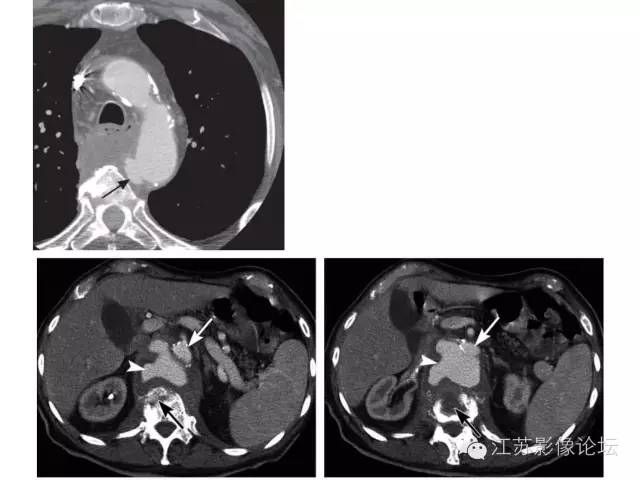

急性主动脉综合征(AAS)是最终可能进展为主动脉破裂的潜在威胁生命的一系列情况。该综合征包括主动脉夹层(AD)、壁内血肿、穿透性溃疡和不稳定的胸主动脉瘤。多排螺旋CT(MDCT)对AAS的诊断是至关重要的,特别是在急救方面,由于它的速度、精度和准备情况。 医学百科网 | YxBaike.Com

主动脉夹层是最常遇到的急性主动脉综合症,如果得不到迅速确诊和处理,也是最有可能造成灾难性后果的。

在主动脉夹层鉴别真假腔至关重要,一系列CT表现如“beak sign鸟嘴征”,主动脉“cobwebs蜘蛛网”,这样的表述有着明确的鉴别意义。平扫CT的价值,特别是用于壁间血肿的诊断也加以论述。各种临床和影像学表现共同类似主动脉综合症的情况也是很常见。 医学百科网 | YxBaike.Com